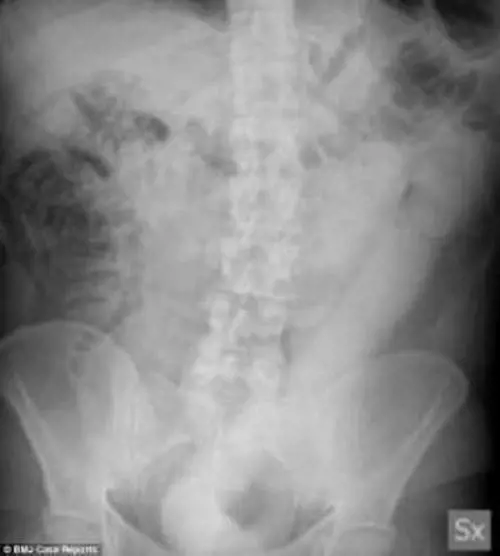

Un caso bizzarro e imbarazzante a Milano: un uomo si è presentato all'ospedale Niguarda con un dildo di 60 centimetri nel retto